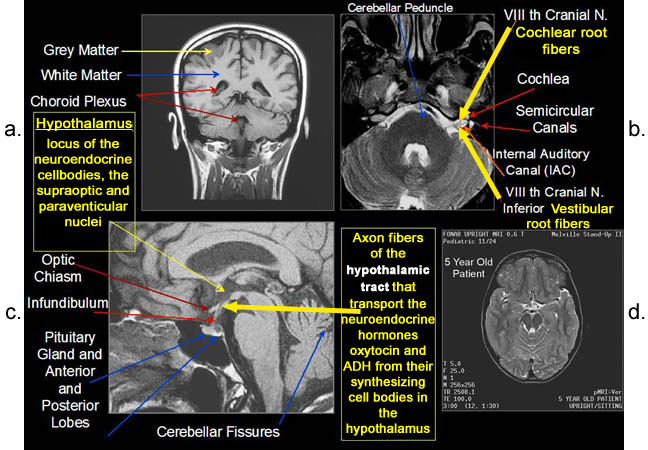

Figure 8.

Figure 8a-8d.

Further examples of the exceptional anatomic detail

made visible by the DISCOVERY

of Damadian of the pronounced differences in the decay

rates (relaxations) of the NMR signals

of the body's normal tissues (Figure

6). The DISCOVERED

differences supply the pixel amplitude differences

"PIXEL CONTRAST (IMAGE DETAIL)"

that produce, for the first time in medical history,

the detailed visualization of normal human anatomy

MRI is noted for. Note the visualization of the

vestibular and cochlear nerves

WITHIN

the internal auditory canel (Figure 8b) and the visualization

of the hypothalamic

tract (that transports hormones from

the brain) WITHIN

the pituitary stalk. (Figure 8c)